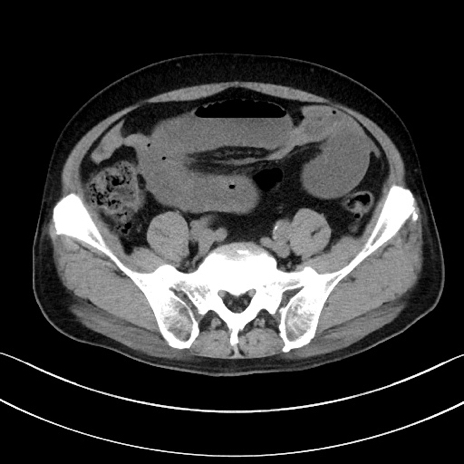

症例15(横断像)

【症例】70歳代男性

【主訴】腹痛

【現病歴】今朝から腹痛あり。全体的に痛い。特に左上の方。排ガスが今日はない。冷や汗が出る。

【既往歴】直腸癌術後

【身体所見】左側腹部〜上腹部に圧痛あり。腹膜刺激症状明らかなではない。軽度反跳痛。左下腹部に術後瘢痕あり。

【データ】WBC 7700、CRP 0.02